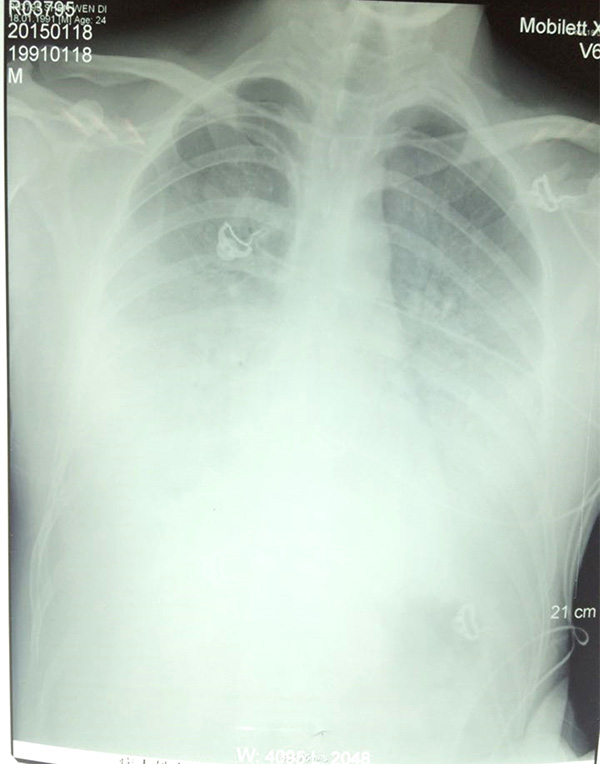

陶園的肺部CT

1月18日,陶園使用氣管插管接呼吸機輔助呼吸;1月19日,病情持續(xù)惡化,白肺進一步加重,CT上整個肺部幾乎都是白色;1月20日,三院專家和市第一人民醫(yī)院兩位專家以及來自上海第二軍醫(yī)大學附屬長海醫(yī)院的專家經(jīng)過會診,決定最后使用CRRT(體外血液凈化以替代受損的腎功能)和ECOM(體外血液循環(huán)替代受損的心肺功能)試一下。

當天下午,醫(yī)生通過會診,發(fā)現(xiàn)陶園的雙肺均有炎癥,出現(xiàn)“白肺”跡象,這說明此時肺部已經(jīng)無法完成氧氣交換。而“白肺”最常見的病因是感染,其次是彌漫性肺泡出血綜合征、急性呼吸窘迫綜合征等。